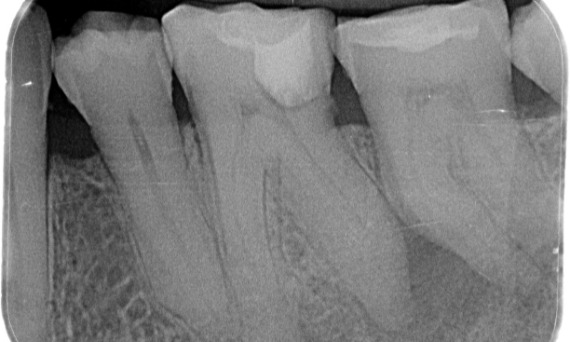

Antes: Radioluscência periapical associada principalmente à raiz distal e perda da lâmina dura na raiz mesial.

Depois: TruNatomy foi escolhido neste caso para permitir uma abordagem alavancada da cárie dental e um foco na preservação da dentina pericervical, especialmente no aspecto mesial, onde o dente teve uma restauração mais mínima.

Dr. Jonathan Cowie (especialista em endodontia)

Bath, Reino Unido